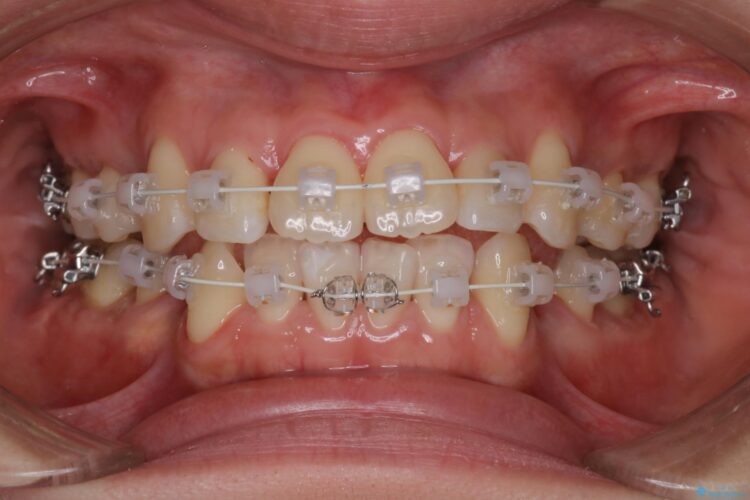

重度の叢生が認められたため、上下左右4番目の歯を抜歯しワイヤー矯正治療を行いました。

前歯のデコボコが改善され、噛みあわせも綺麗になりました。

歯肉退縮もなく、予定通りに治療を終えることができ大変ご満足いただけました。